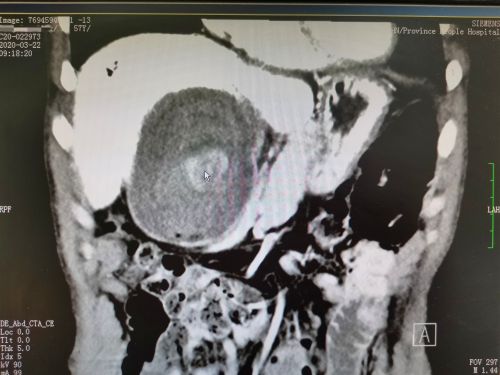

ct能明显看到右上腹结石占位(鼠标所示)。

惊恐的李先生经多方打听,找到捷克论坛 肝胆胰微创外科尹新民主任医师处就诊。尹新民教授详细询问病史并仔细查阅CT及磁共振影像资料发现,李先生无连续肝外胆管,肝内有积气,据此推断他曾做过胆肠内引流手术,此次应是“桥袢巨型结石”引发右上腹疼痛。

因患者曾做过两次开腹手术,腹腔粘连严重,结石又巨大,为保障患者安全并减少手术创伤,经过多次术前讨论后,331日,由尹新民教授团队为其实施腹腔镜腹腔粘连松解、胆肠吻合口切开取石、胆道探查、胆道镜肝内清除结石、桥袢空肠整形、胆肠吻合口重建术。手术历时近7个小时,取出结石约250g,其中最大的直径达13cm,创下国内腹腔镜桥袢结石手术取出结石最多的纪录。